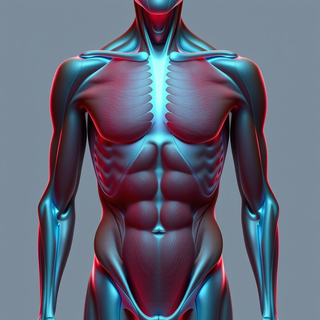

Generate ultra-realistic microscopic imagery for medical research.Open

Generate ultra-realistic microscopic imagery for medical research.Open